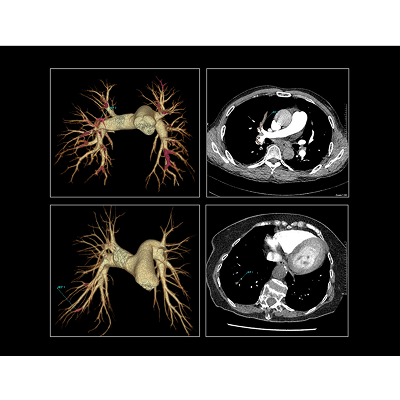

联影智能CT肺栓塞智能分析系统能够提供PE分诊预警、栓子检出和量化、肺血管智能分割和重建等功能,帮助医生及时诊断PE,鉴别诊断急性胸痛患者。同时,肺栓塞智能分析系统能够自动、准确地进行心室测量和肺动脉测量,提示右心室增宽和肺动脉增宽等PE相关风险征象,为早期PE检测和风险分层提供参考,辅助医生制定更优的诊疗方案,改善预后。

联影智能CT肺栓塞人工智能可一键智能分割、重建完整肺血管和栓子,360°展示肺动脉走行和栓子分布位置;高灵敏检出和定位栓子,提供量化分析,并自动计算RV/LV和PA/Ao,全面辅助诊疗,为PE的早期识别和临床风险分层提供强有力的智能工具;而快速分诊预警更是能够助力危急患者尽早进入诊疗环节。此外,AI可智能生成文本报告和归档图像,支持一键胶片打印。通过对救治全流程的加速优化,AI能够辅助医生快速识别隐匿肺栓塞,让胸痛患者跑赢生死竞速。